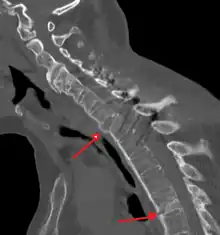

Imaging

X-rays

The earliest changes demonstrable by plain X-ray shows erosions and sclerosis in sacroiliac joints. Progression of the erosions leads to widening of the joint space and bony sclerosis. X-ray spine can reveal squaring of vertebrae with bony spur formation called syndesmophyte. This causes the bamboo spine appearance. A drawback of X-ray diagnosis is the signs and symptoms of AS have usually been established as long as 7–10 years prior to X-ray-evident changes occurring on a plain film X-ray, which means a delay of as long as 10 years before adequate therapies can be introduced.[26]

Options for earlier diagnosis are tomography and MRI of the sacroiliac joints, but the reliability of these tests is still unclear.

CT scan showing bamboo spine in ankylosing spondylitis